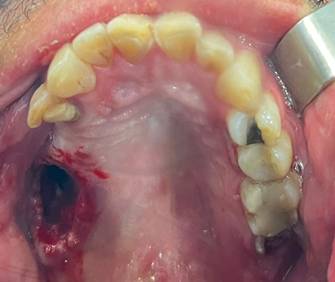

En la figura 1 se muestra la comunicación bucosinusal provocada por la extracción de la pieza dental # 1,7

Figura 1. CBS del sector posterior, pieza dental #1.7